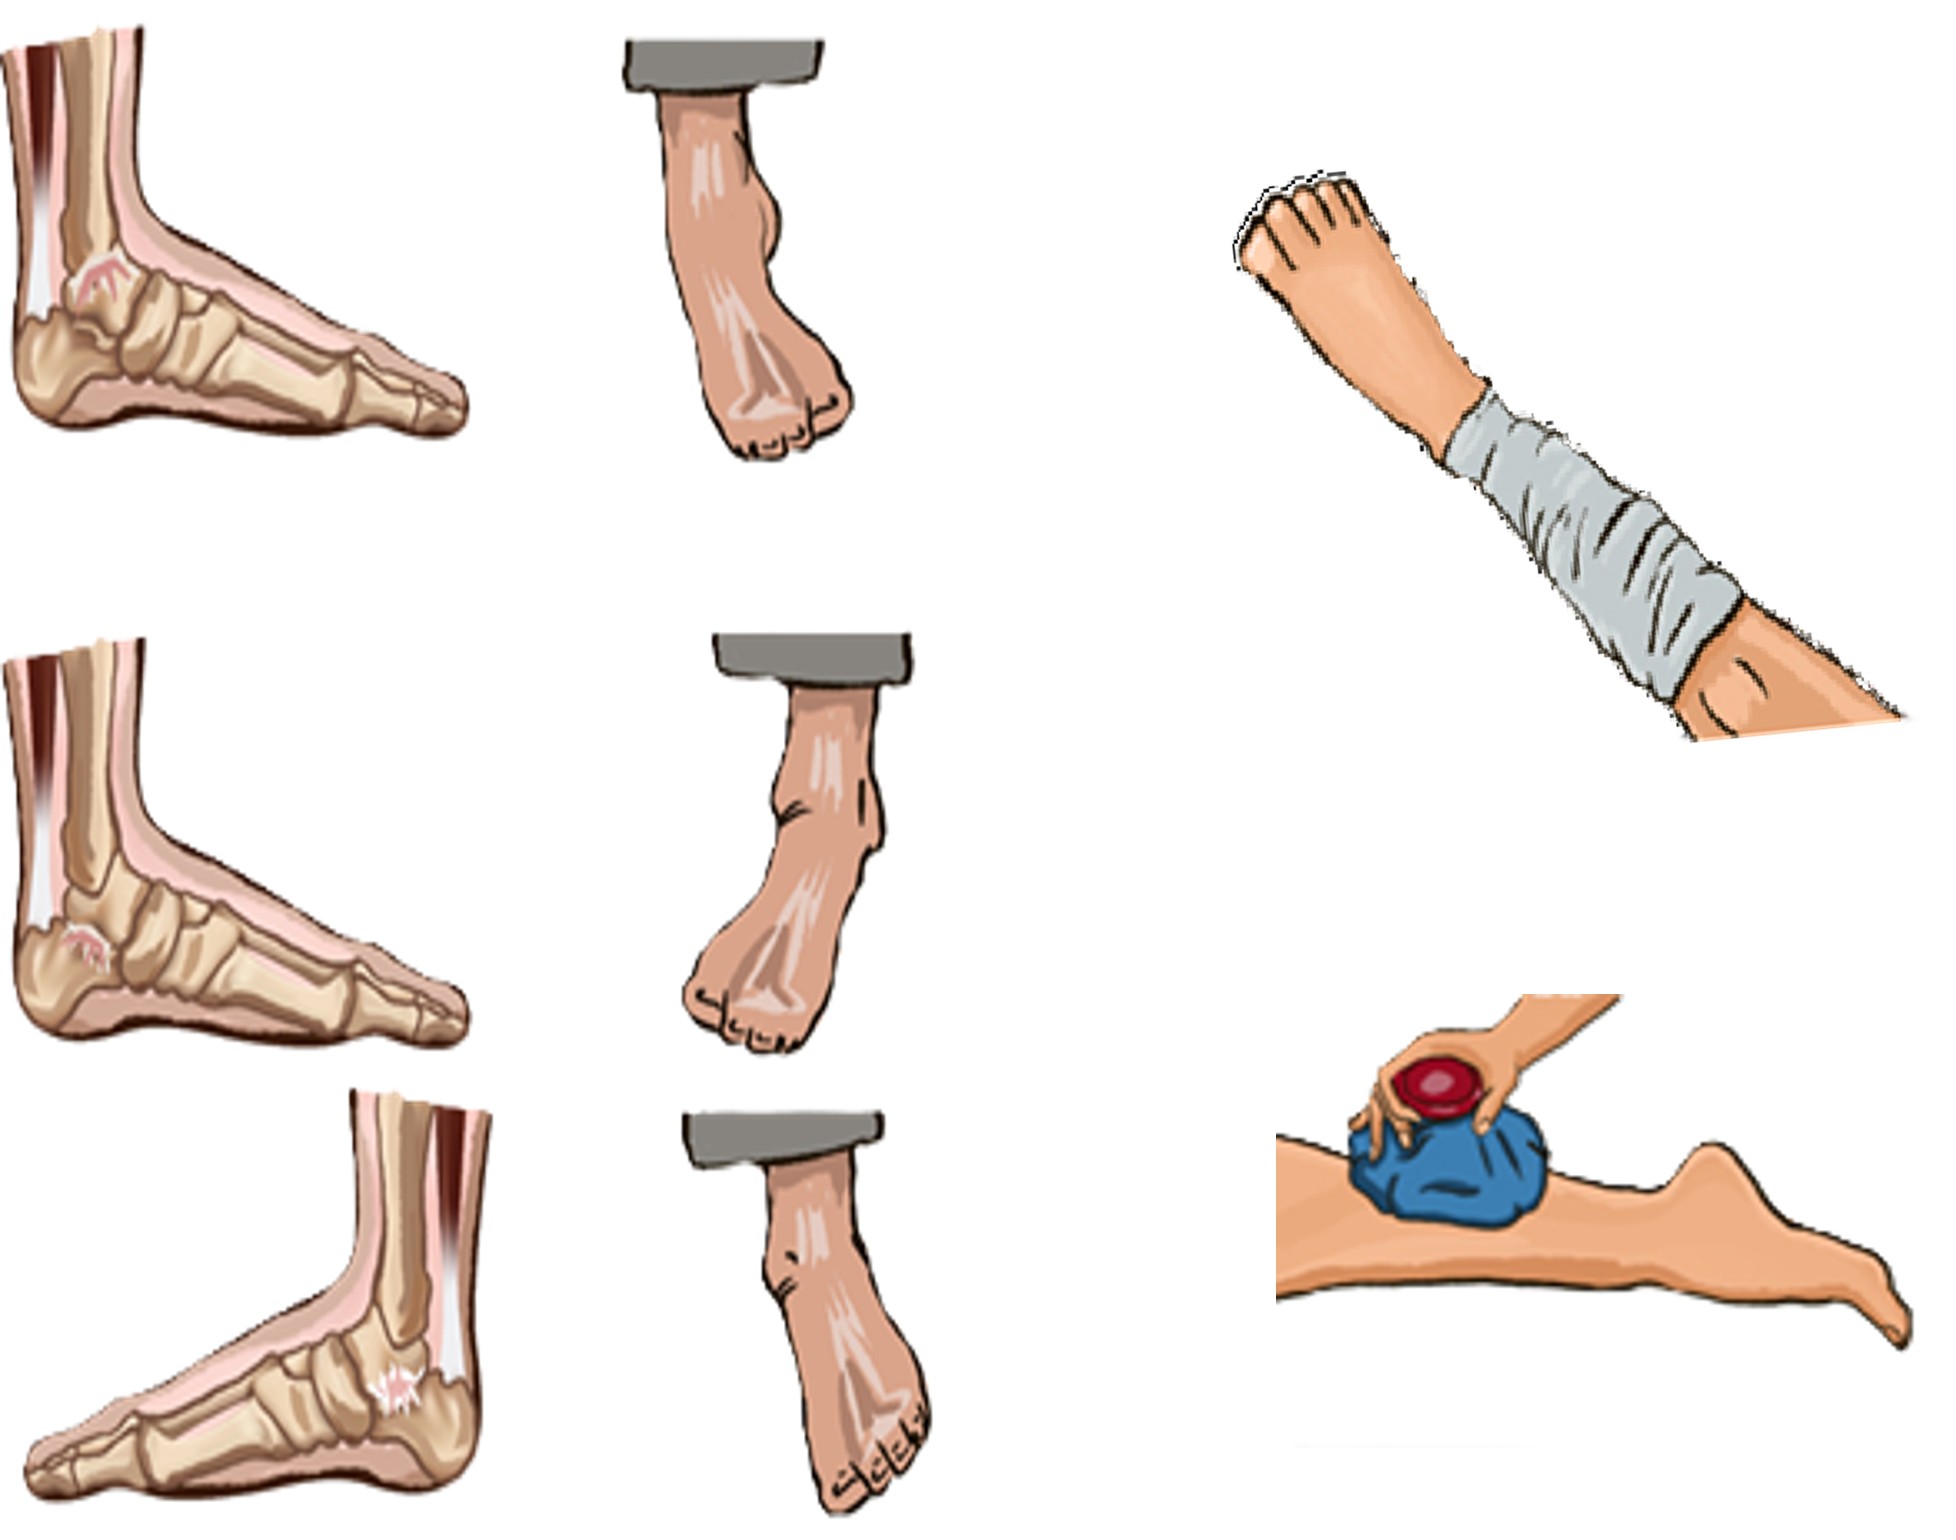

Εξάρθρημα

Συμπτώματα:

- Παραμόρφωση

- Δυσκολία στην κίνηση

- Έντονος πόνος

- Έντονο οίδημα

Πρώτες Βοήθειες:

- Κλήση 112/166

- Αποφυγή μετακίνησης εξαρθρωμένου οστού

- Τοποθέτηση ψυχρών επιθεμάτων στην άρθρωση